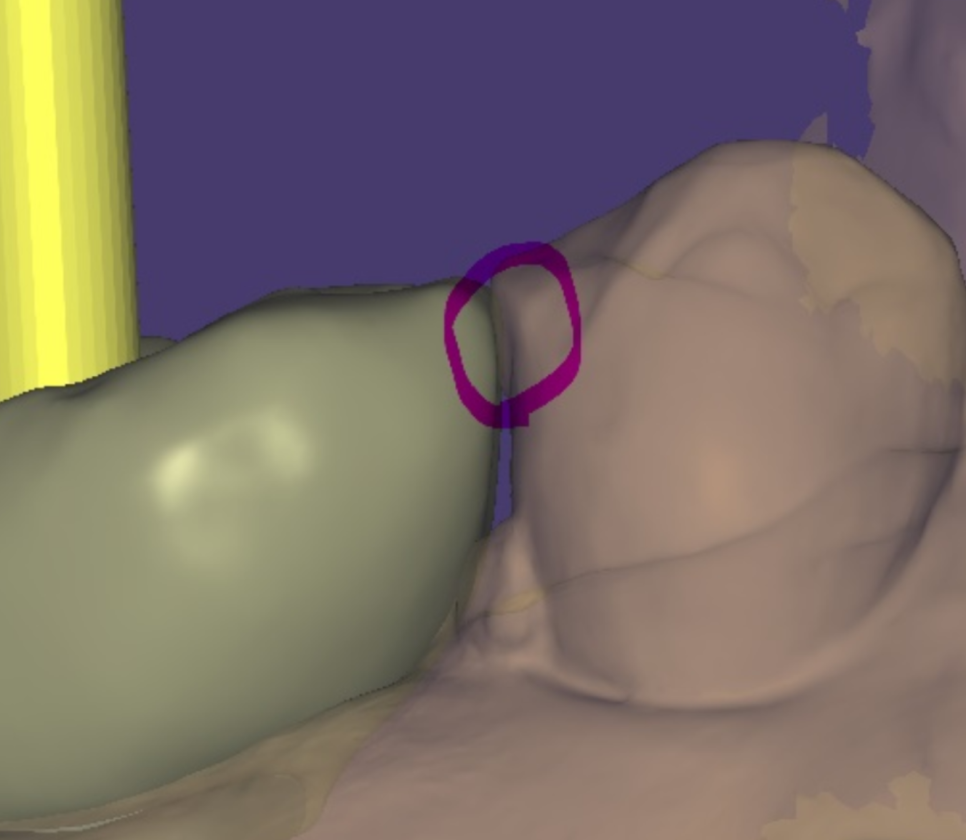

구강스캐너를 사용하여 디지털로 제작하면 수정 가능성이 크게 줄어듭니다.

240611 보철의 두께감이 두꺼워도 볼을 씹을 수 있습니다.

두번째로 보철물의 높이나 형태 문제입니다.

보철의 두께가 조금만 두꺼워도

환자분들은 두껍다는 것을 바로 아세요.

튀어나오는 느낌을 받으신다고 합니다.

반복적으로 씹는다면 보철물의 두께와 형태를

다시 만들어줄 필요가 있습니다.